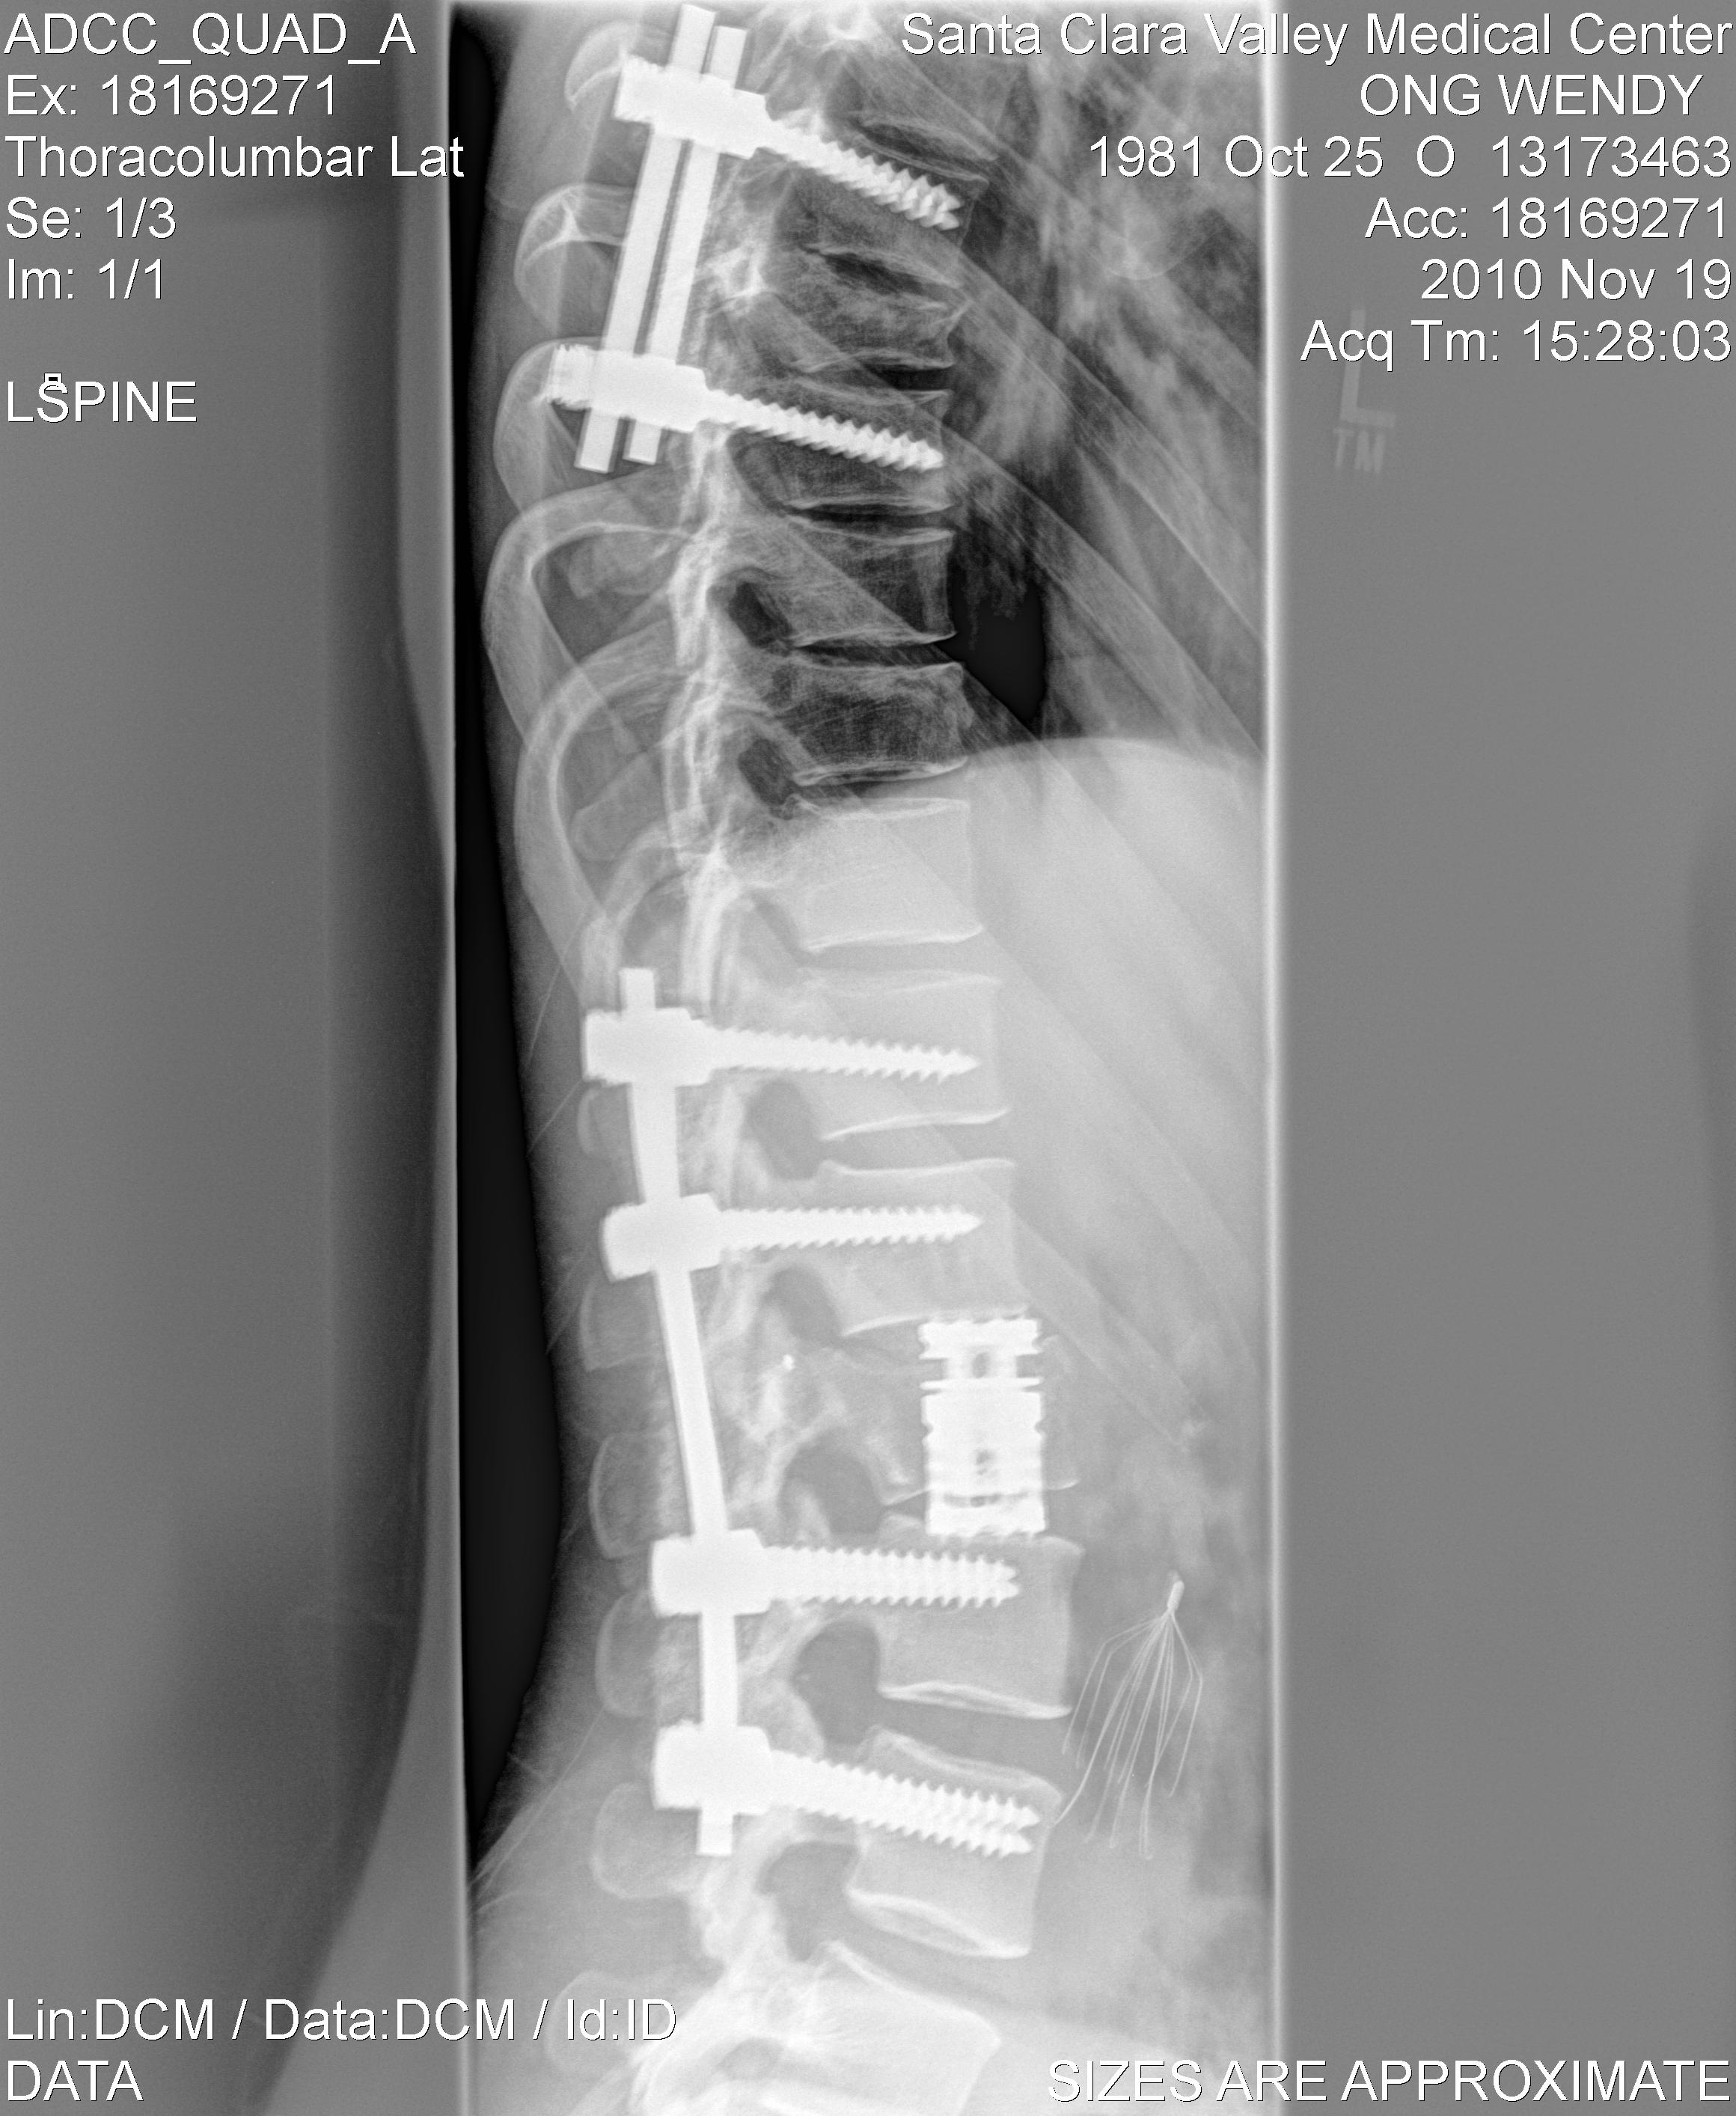

In October 2010, while sport-climbing at Owens River Gorge near Bishop, CA, I was dropped and fell close to 200 feet (70m), smashing to the ground. The result was a T-10 incomplete Spinal Cord Injury, Cauda Equina Syndrome (basically all the nerves at the base of my Spinal Cord/Sacrum were shredded up), shattered pelvis, disintegrated sacrum, exploded L-vertebrae, a paralyzed left-leg and a lifetime of chronic pain and impaired bowel/bladder function.

Aside from the vertebral fractures and Spinal Cord damage, my L2 vertebra exploded upon impact, my pelvis broke in multiple places and my sacrum was reduced to a collection of pebbles. The process of piecing back together humpty-dumpty was a long, arduous and very painful one.